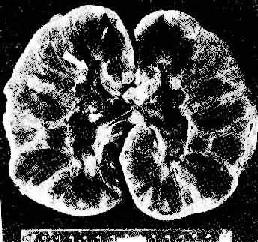

(2)血管型排斥反应:主要为抗体介导的排斥反应(CMC,ADCC和免疫复合物形成),往往在稍后出现,以突出的血管病变为特征。表现为肾细、小动脉的坏死性血管炎,可呈弥漫或局灶性分布。免疫荧光证实有免疫球蛋白、补体及纤维蛋白沉积,肾小球毛细血管袢亦可受累。纤维蛋白样坏死的血管壁内常有淋巴细胞、泡沫细胞及中性粒细胞浸润,腔内可有血小板凝集、血栓形成(图4-5)。后期的血管内膜纤维化,管腔狭窄。间质内常有不同程度淋巴细胞、巨噬细胞及浆细胞浸润。肉眼观,肾常明显肿大,呈暗红色并有出血点,有时可出现黄褐色的梗死灶,可伴有肾盂及肾盏出血(图4-6).临床上,移植肾出现功能减退,大剂量免疫抑制剂疗效不佳。

肾移植急性排斥反应

图4-6 肾移植急性排斥反应

肾肿胀,明显出血,肾盏及肾盂中充满血块